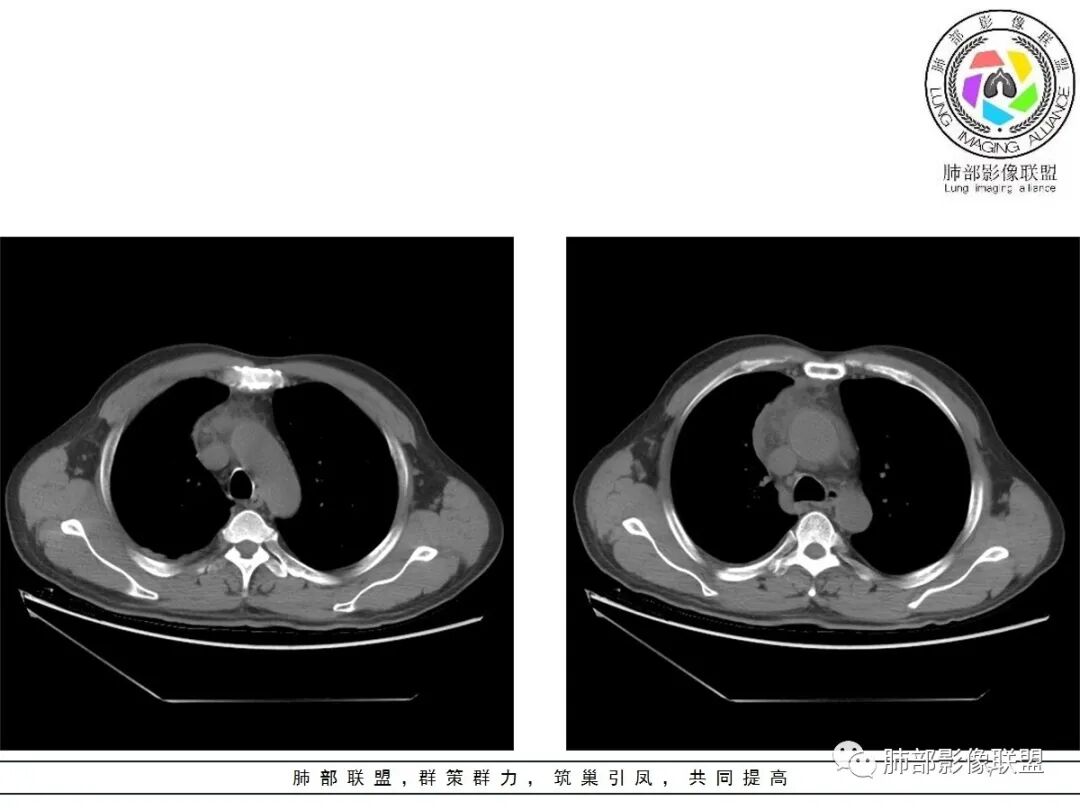

小赵:这个是3月15日的视频

小赵:第二个是3月19日的视频

周围脂肪间隙密度增高,内部小点状很低密度影

右侧少量胸水

2.胸膜掀起,右侧内乳动脉略增粗,定位右前上纵隔内占位。

3.右上纵隔囊实性占位,边界清楚。中央见点状脂肪密度影,边缘见一点状钙化影,增强不均匀环形强化。

第一次的检查符合胸腺瘤影像学改变,短期内的形态学改变及突然出现的边界模糊或浸润等,符合出血或炎症。